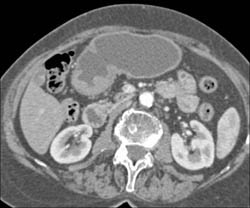

Antral Carcinoma